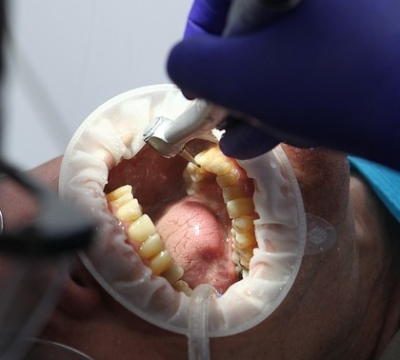

- 발치를 시작합니다. 마취가 되어 통증은 없지만 의사 선생님이 힘주어서 이를 빼는 것이 온전히 느껴집니다.

- 아랫니는 쉽게 빠졌지만 윗니는 중간에 한번 부러져서, 선생님께서 오랜 시간 애먹으셨고 저도 머리가 기울어질 정도로 압력을 받으면서 이가 빠지려고 우드득 하는 소리를 듣는 게 몹시 고통스러웠습니다.